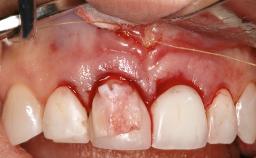

Resective Surgical Treatment of Peri-Implantitis Including Implantoplasty

Myroslav Solonko, Ignacio Sanz Sánchez, Mariano Sanz

In this case, Myroslav Solonko, Ignacio Sanz Sánchez and Mariano Sanz present a treatment that aims to eliminate exposed implant threads by modifying the implant surface, converting a moderately-rough surface into a smooth surface.

A 63-year-old male patient was referred to the post-graduate periodontal clinic of the Complutense University of Madrid for the treatment of peri-implantitis. According to the patient’s record, all his maxillary teeth had been extracted ten years previously due to severe periodontitis, and a full-mouth implant-supported restoration on eight implants was placed. No supportive periodontal therapy was provided apart from occasional check-ups by the restorative dentist.